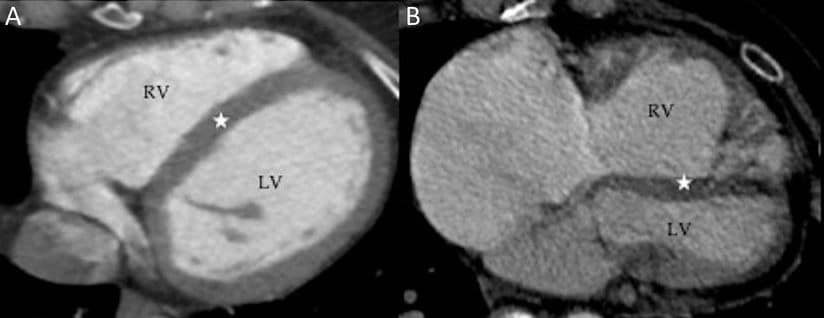

Right: RV dilatation and hypertrophy compressing the LV, creating “clockwise” rotation of the heart

The term “clockwise rotation” describes the apparent rotation of the heart as viewed from below in standard CT/MRI cross-sectional imaging views. High pulmonary pressures in PE cause acute RV pressure overload and dilatation, compressing the interventricular septum (IVS). Ensuing RV dysfunction and hypokinesis worsens these changes, particularly in the apical region. Leads V5-6, which usually face the LV wall and reflect LV depolarisation directly, are subsequently orientated over the IVS. The R/S transition point thus shifts rightwards towards V6.